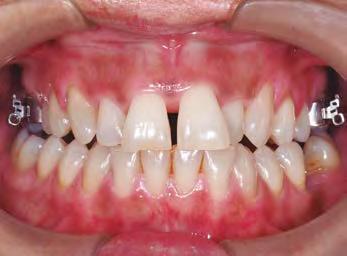

–Corticotomías y Ortodoncia. Ampliando límites del movimiento dental, por la Dra. Aranzazu Senosiain y cols. [50]

–Tratamiento de un caso de Ortodoncia y Cirugía Ortognática con placas preformadas y tecnología 3D, por la Dra. Elena Bonilla Morente y cols. [62]

–Uso del anclaje esqueletal como alternativa eficiente en el manejo ortopédico de clases III por deficiencia de maxilar superior, por el Dr. Carlos Becerra y cols. [74]

–MARPE, una alternativa a la disyunción en el paciente adulto, por el Dr. Enrique Solano y cols. [88]